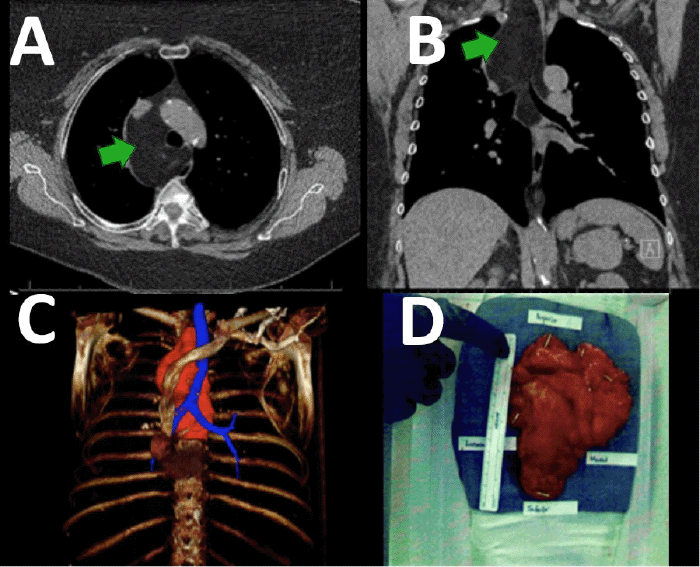

The second case involves a 65-year-old female who presented after a chest X ray was performed for a traumatic rib injury, revealing a retrocardiac mass abutting her esophagus. This measured 6.5 × 8.2 × 13.0 cm on CT scan (Figure 2). The patient underwent esophagogastroduodenoscopy with esophageal ultrasound and fine-needle aspiration. Histology was consistent with a lipoma. As a result of the large size, associated compressive effects on adjacent mediastinal structures, and a theoretical risk of degeneration into a malignancy for long-standing giant lipomas, surgical intervention was recommended. The patient underwent resection via a right lateral thoracotomy. Nearly the entire dissection was performed bluntly by palpation, with the mass easily shelling out and off of surrounding structures in one piece. Operative time was 104 minutes. The lipoma was much larger than the imaging revealed, measuring 17.8 × 13.2 × 3.1 cm. Postoperatively, the patient experienced no adverse effects and was discharged on day 5 without complications on follow-up.

Figure 2. A) Axial CT Scan (green arrow denotes mass), B) Coronal CT Scan (green arrow denotes mass), C) 3D Reconstruction (mass in red), and D) Resected Lipoma. Published with Permission